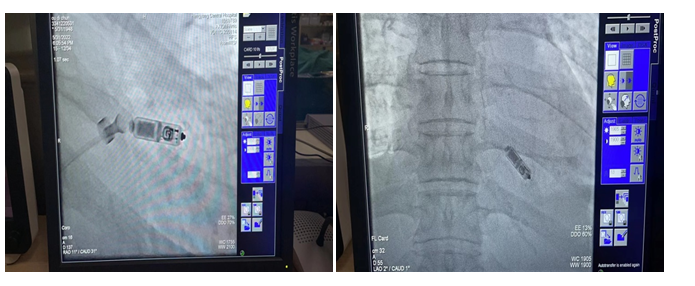

该患者为74岁男性,因二度Ⅱ型房室传导阻滞及三度房室传导阻滞由衡阳市中心医院内分泌科转入心血管内科一区,既往“糖尿病、高血压病、冠心病、高脂血症、脂肪肝、前列腺增生”等病史。转科后,赵庆禧主任带领主管医生谷乐辉对该病人进行了详细的体格检查及病史问询,组织介入团队进行了缜密的术前讨论,与患者及家属充分沟通后,选择了Micra无导线起搏器。5月31日下午,赵庆禧团队密切配合,仅用30分钟时间,通过股静脉穿刺,将起搏器成功植入右心室。目前,该患者恢复良好,已于6月3日出院。

据悉,Micra无导线起搏器是世界最小的起搏器,类似于胶囊大小,其长度为2.59cm,重量仅有1.75g,比传统起搏器体积减少93%。整个手术过程大约半个小时,植入成功率非常高,该起搏器无需植入心内膜导线,也无需在胸前皮下制作囊袋放置脉冲发生器,减少了创伤及感染的风险。而且Micra无导线起搏器直接植入在心腔内,无切口,除了美观外,患者在植入后几乎感觉不到起搏器的存在。术后进行短时间的血管穿刺口管理即可下床活动,术后并发症极少,无需严格卧床休息,使患者的生理和心理上均得到最大的放松。